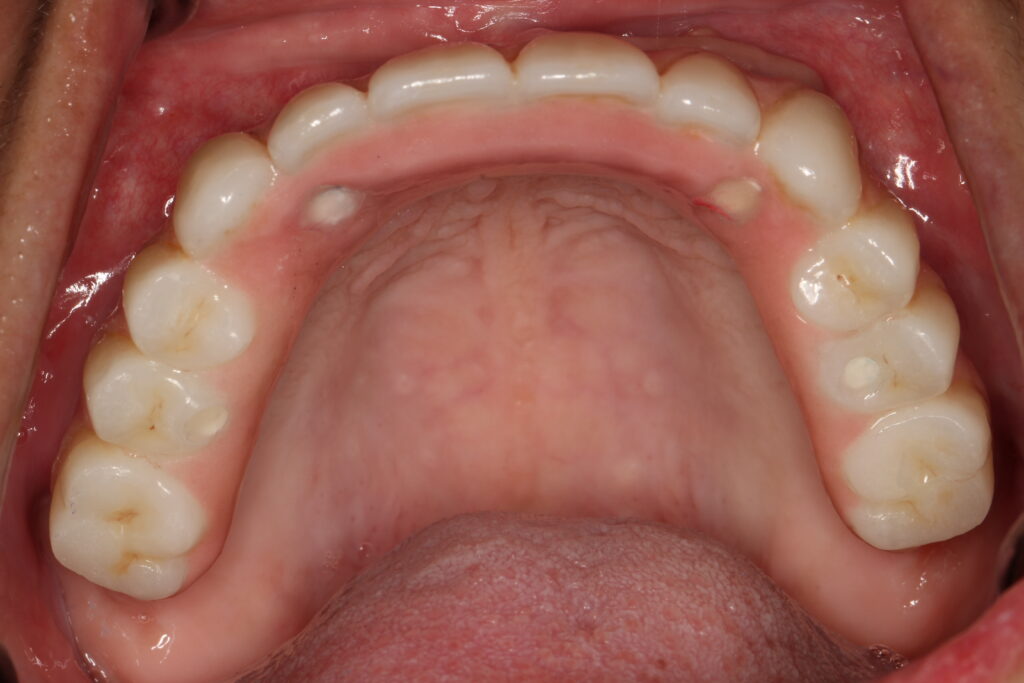

A selection of full arch fixed implant bridge patients after 5 years of wear